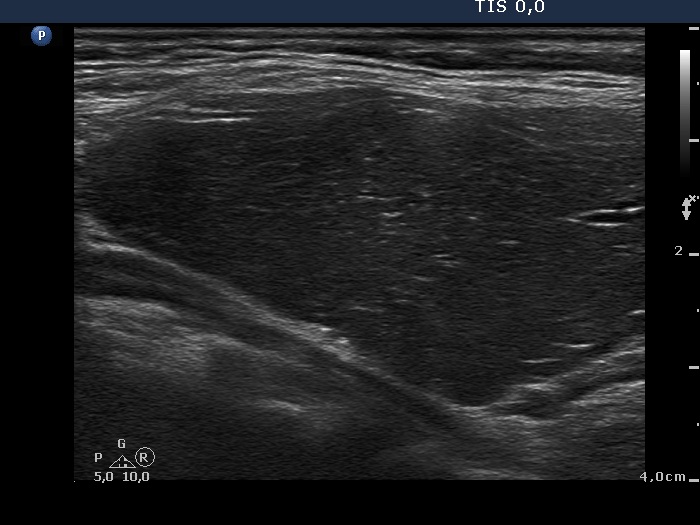

Consecutively operated patients with autoimmune thyroid disease - case 24 (790) (ultrasonographic picture 5)

Upper part of the left lobe, longitudinal view.